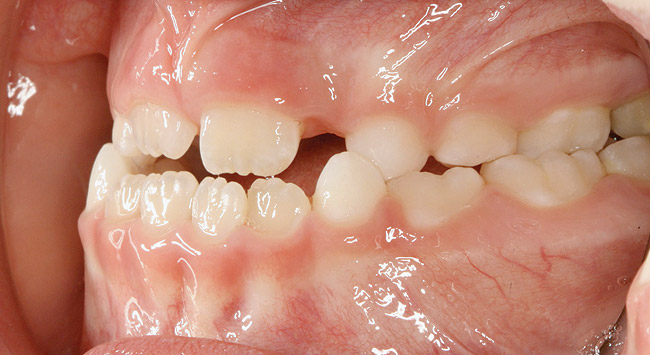

(9.) An

Figure 9

(10.) Narrow maxilla with tooth wear and bilateral crossbite.

Figure 10

(11.) Adenoidal tissue blocking the velopharyngeal airway.

Figure 11

(12.) Class II Angle classification with worn dentition and anterior open bite.

Figure 12